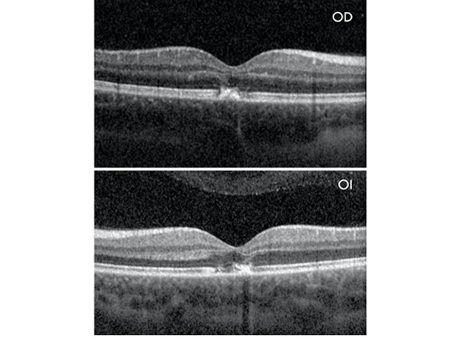

La OCT de AO evidencia disrupción de la elipsoide asociado a banda curvilínea hiperreflectiva que se extiende desde el epitelio pigmentario retiniano hasta la capa plexiforme externa siguiendo la capa de fibras de Henle (Imagen 2).

Imagen 2

La evolución de los hallazgos de OCT se documentó al día 1, 2 semanas y 6 semanas después de la lesión. Se pudo observar la evolución de las bandas curvilíneas verticales de hiperreflectividad y su resolución a las 2 semanas con presencia de pequeñas cavidades hiporreflectivas próximas a la fóvea. A las 6 semanas de inicio del cuadro se observa resolución de los hallazgos a nivel de OCT con escasas alteraciones a nivel de capa elipsoide en OD y una AV de 20/25 en AO (Imagen 4).